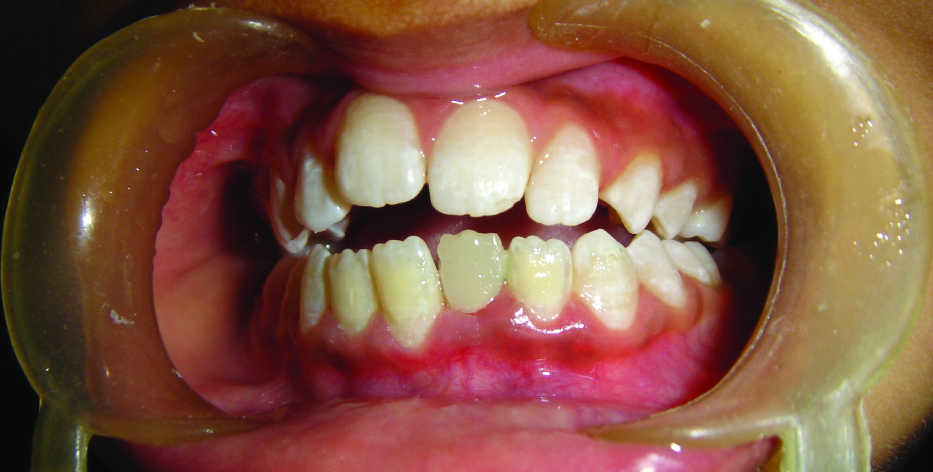

A 12-year-old female patient visited the Department of Pediatric Dentistry with a complain of broken left lower front tooth since four months. The patient did not complain of any pain [Table/Fig-1]. The parent of the patient told that the girl had a fall two years back in which the lower front tooth got broken. There was pain and tenderness reported at that time and they had visited a dentist for the same. On further enquiry it was revealed that the mentioned tooth had been root canal treated six months back and restored but the restoration came out within a month. The re-restoration also did not last more than 15 days. On examination lower left central incisor was fractured and there was neither pain reported nor tenderness to percussion. The tooth structure was less for a composite make-up or a crown. After thorough examination it was decided to go for a post and core and composite make up. As it was an anterior tooth in a young patient it was decided to go for fibre-reinforced composite (Ribbond, Ribbond THM, Ribbond inc.Seattle,WA) as post and core material as it is esthetic and has adequate strength. As the tooth was adequately obturated [Table/Fig-2], preparation of the canal space was done [Table/Fig-3,4]. The use of ribbond does not require additional tooth preparation as is required for metal posts. The remaining tooth structure being less, rubber dam isolation could not be accomplished and we decided for high suction evacuation with cotton rolls to be suitable for isolation. Gutta percha was removed using gutta percha solvent until the desired length for post was achieved. The post hole was shaped using Gates Glidden drills (Roydent, West Palm Beach, FL), cleaned with 5% sodium hypochlorite and dried. The width of Ribbond is to be decided on the root canal space available. The depth of the post space was measured using a periodontal probe, and a 3-mm-wide Ribbond was cut using special scissors provided with the kit (Ribbond starter kit, Ribbond THM, Seattle), measuring twice the depth of the post space and 3–4 times the height of the core build-up [Table/Fig-5] and placed in dual cure adhesive resin and set aside in light protected container. The root canal wall was etched, washed thoroughly and then air-dried gently. Excess water was removed from the post space using paper points . The dual cure adhesive resin (Ed Primer II A&B) was applied using a microbrush and gently air-dried to evaporate the solvent. Dual cure resin cement was then placed inside the canal space. The Ribbond was removed from the resin and the excess resin was removed using a hand instrument [Table/Fig-6], folded in a V-shape and coated with dual-curing resin cement (Panavia, Kuraray Medical Inc., Japan). The piece of ribbond was then placed in the post space in a labial-lingual direction with a periodontal probe [Table/Fig-7]. Excess resin cement was removed, and the cement was cured for 20 s. The two protruding ends of the Ribbond strips formed the reinforcement for the core build up to replace the lost coronal portion of the tooth. The remaining resin mix from the syringe was extruded onto this framework to create a core resembling almost like the shape of a lower central incisor. The space between the protruding ribbon ends was filled with resin so as not to leave any voids. Composite resin was also placed so as to cover the ribbon ends completely and leave none of them exposed on the outer surface of the core. All the material was thoroughly light cured to create a set surface. The material was left in the mouth for a couple of hours to ensure complete set of the self curing component of the resin mix. The result of this procedure came out to be a single piece post and core, which was bonded onto the root, creating a solid structure without any wedging effect on the root. Moreover, the resin conforming to the inside shape of the canal space ensured no voids and eliminated “fitting” problems normally associated with cast posts. The bands of Ribbond reinforced the resin material and made it extremely strong and durable. Bonding of the entire material also created a single block of post and core, which is the essence sought for favourable occlusal force transmission and for resistance against debonding of the entire unit. The best thing was, there was no metal to mask with the crown since the base shade of the composite was a close enough match to the tooth and was translucent. These strips, although opaque, were white in colour and after being completely encased in the composite, were not visible. However, they did not contribute to the colour of the core in any adverse way. The restorative procedure was completed by building up the tooth using dual cure hybrid composite resin following technique of small progressive build up without any matrix [Table/Fig-8,9]. All these increments were fully light cured. Finishing and polishing procedures were performed using composite contouring and polishing discs. The patient was advised for a crown at a later stage after complete development of occlusion. The patient has been under follow up for two years now with six month follow up intervals and the restoration is still in good condition [Table/Fig-10,11]. As because the occlusion is not yet established we have decided to give crown on a later date.